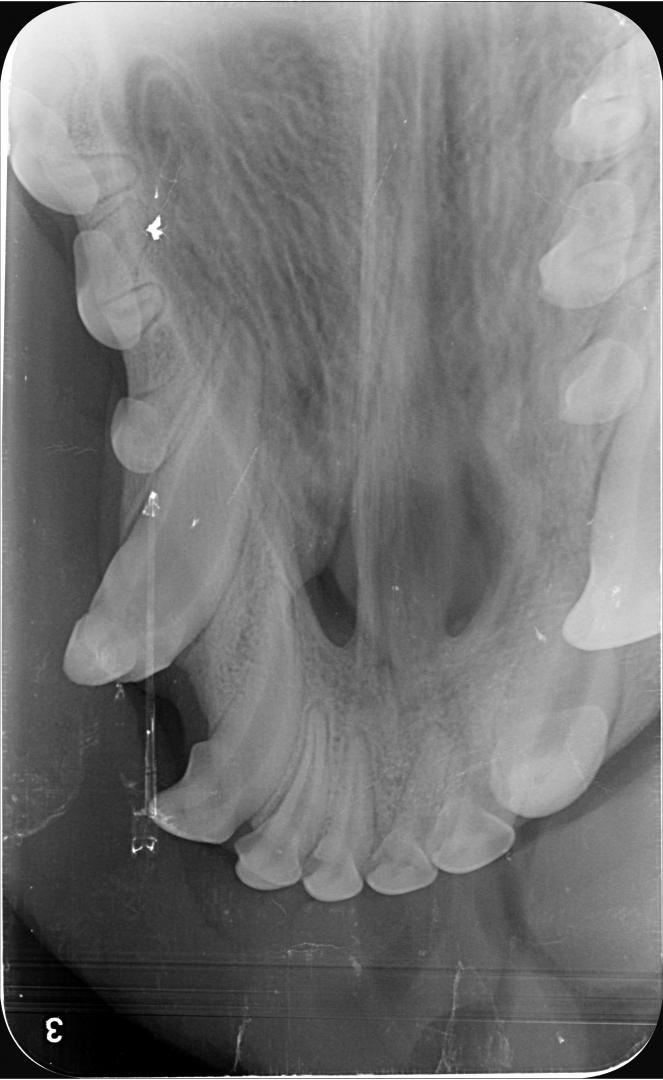

radio croc

Dans le cas d'Alphonse :

- l'apex est fermé (cercle vert) sur les 3 dents concernées ; aucun abcès n'est visible et donc la pulpe ne présente pas de signe de contamination (vérifié également par sondage, le canal n'est pas perméable)

- La couche de dentine semble déjà conséquente et suffisante pour donner une chance à la dent (trait bleu) ;

La décision est donc prise de tenter de la conserver, et de protéger la pulpe en déposant une couche de résine pour combler les surfaces abîmées du croc.